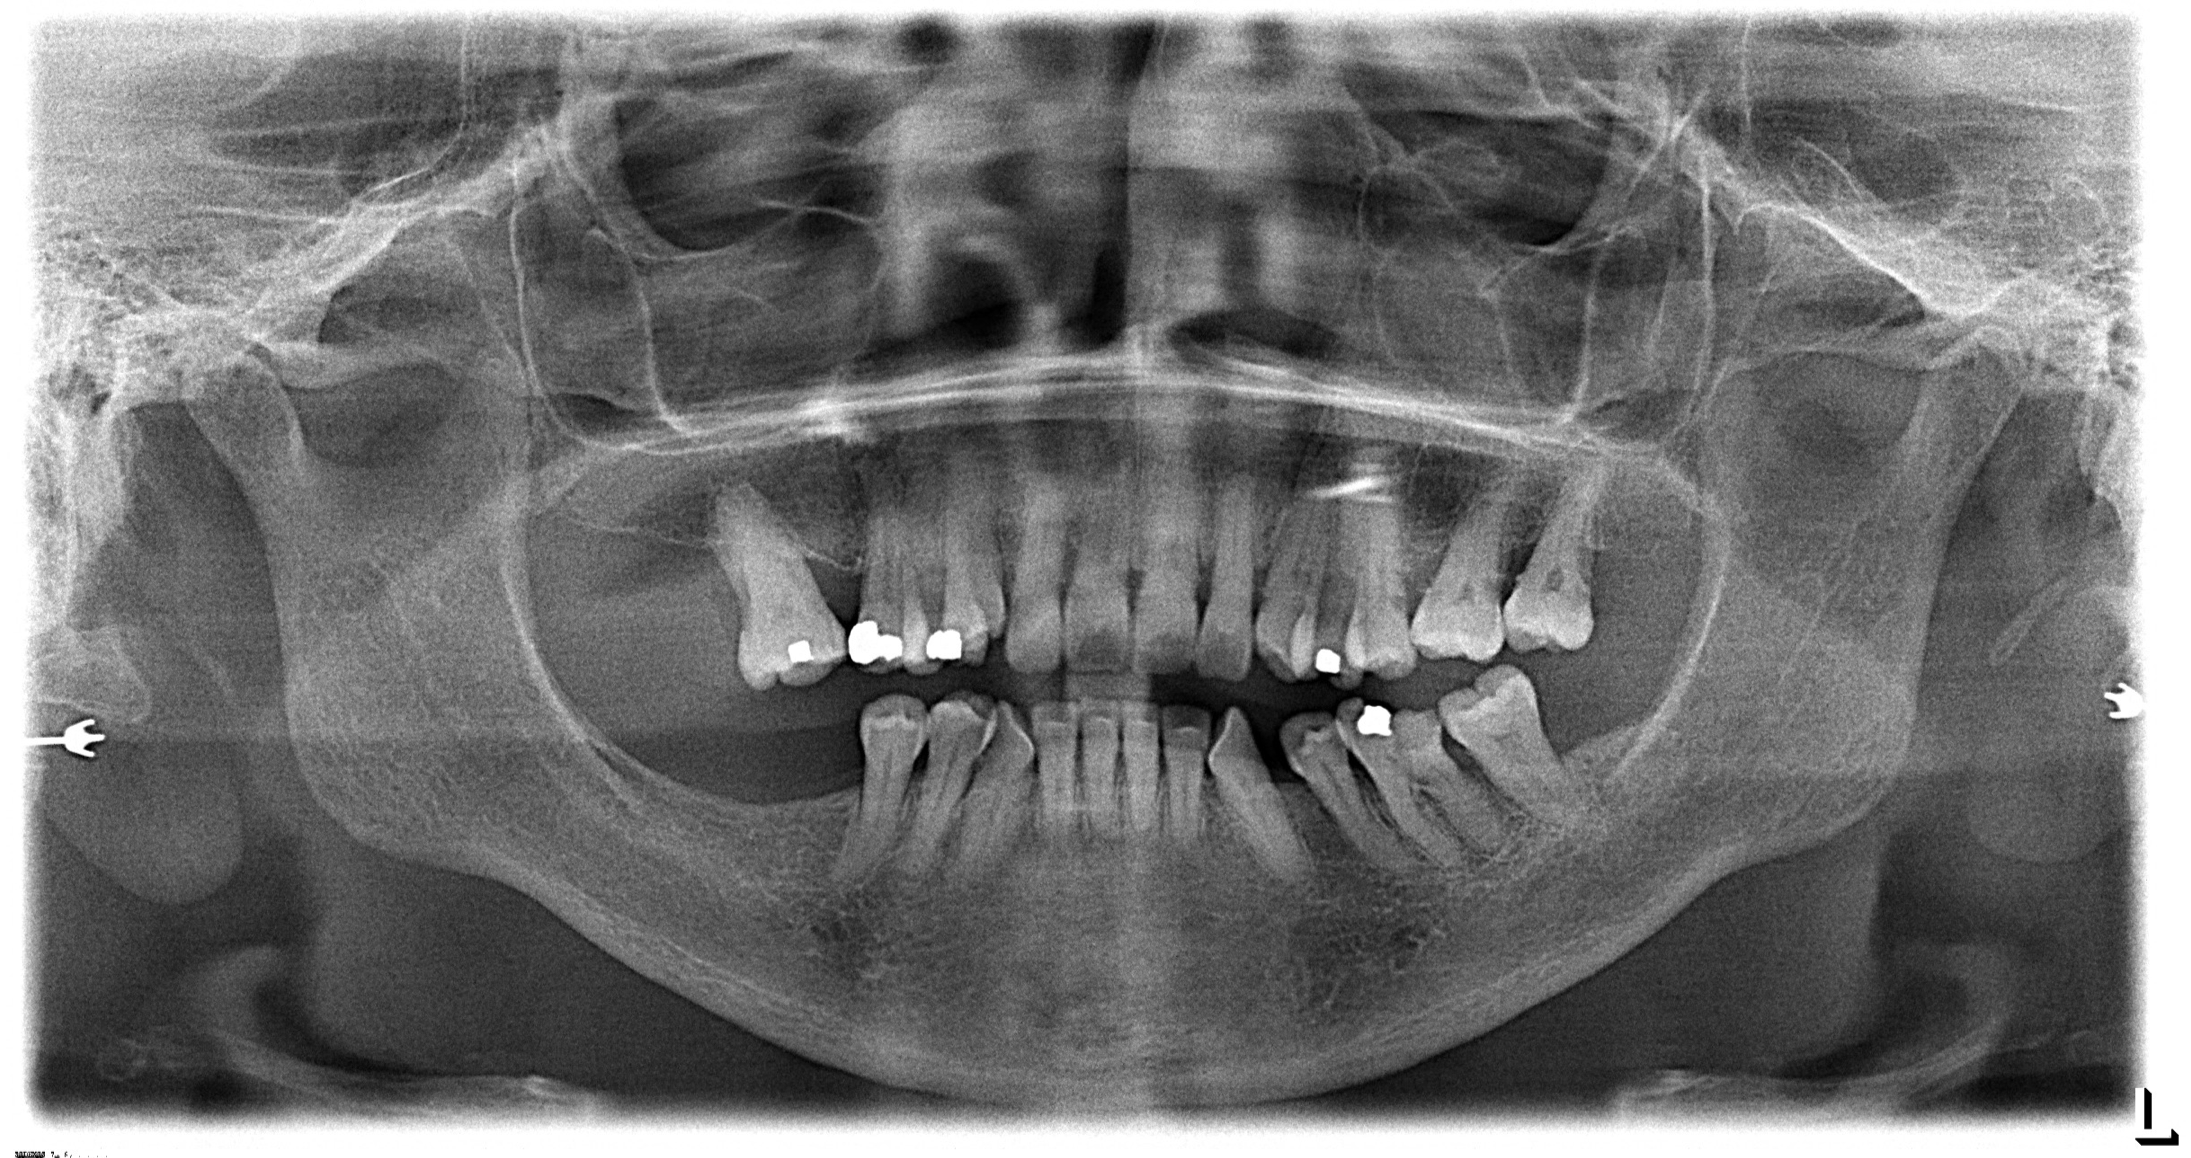

Digital radiography, since its introduction in the mid-1980s, has overtaken conventional screen-film radiography, making it one of the most significant advancements in the dental industry.3 It allows dental offices to acquire a quality image within a matter of seconds (Figure 1). It is a valuable, reliable diagnostic tool for patients of all ages. In children, for example, the primary reasons radiographs are used are for the detection of caries, dental injuries, disturbances in tooth development, and the examination of pathologic conditions other than caries.4 Additionally, 3-dimensional reconstruction of radiographic images is of importance for diagnosis and treatment planning concerning malformations, trauma, tumor investigation, and surgery planning.

Fig 1. Digital radiography allows dental offices to acquire a quality image within seconds.

Figure 1